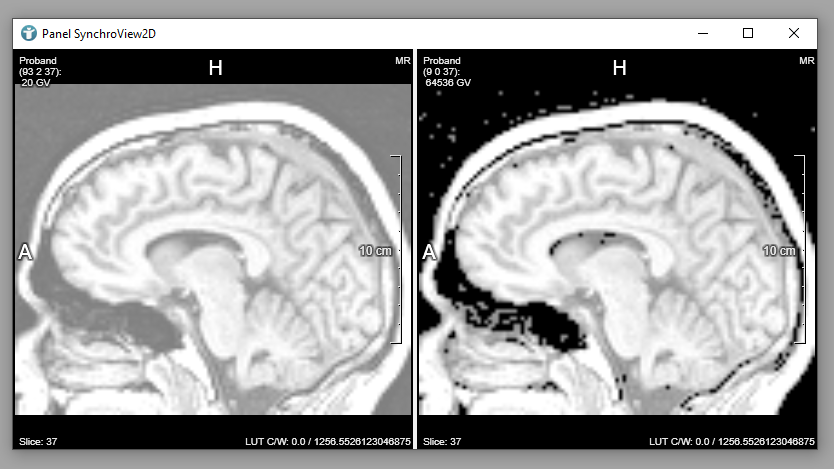

Now, all voxels having a value lower or equal 60 are set to 0, all others are set to 1. The resulting image from the Threshold module is a binary image that can now be used as a mask by the Mask module.

The Mask module is configured to use the Masked Original image. Changing the window/level values in your images now, you can see that the background voxels are not affected anymore (at least as long as you do not reach a very large value).